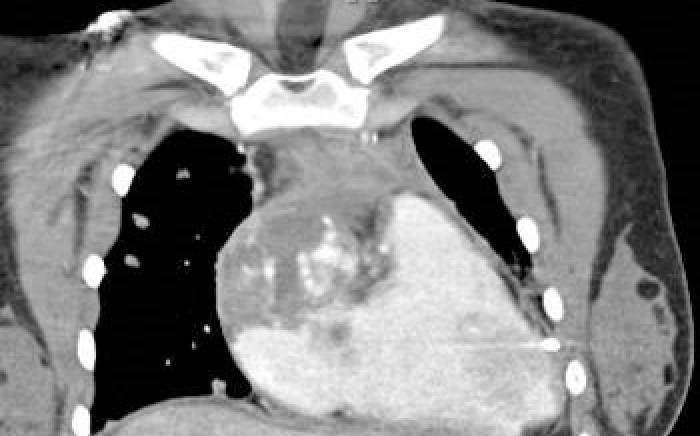

Case Study: "Long Time Coming"

The following case study was used by Andrew J. White, MD, pediatric rheumatologist and director of the St. Louis Children’s ...